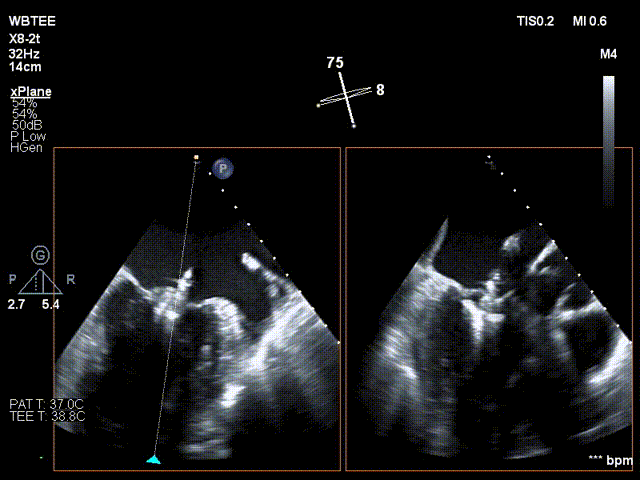

患者全身麻醉消毒铺巾后,建立右侧股静脉入路,在经食道超声指导下精准穿刺房间隔。将可操控导引导管和二尖瓣夹XTR输送系统送入左心房

调整二尖瓣夹轨迹和方向,使其轨迹垂直于二尖瓣环平面且指向心尖,定位于二尖瓣2区且6-12点钟方位

在食道超声王蓓主任的紧密配合下,经食道超声引导后傅国胜教授使用二尖瓣夹准确成功捕获前叶A2和后叶P2反流最严重区域,并予夹合,使二尖瓣在收缩期由大的单孔变成小的双孔,显著减少了二尖瓣反流。